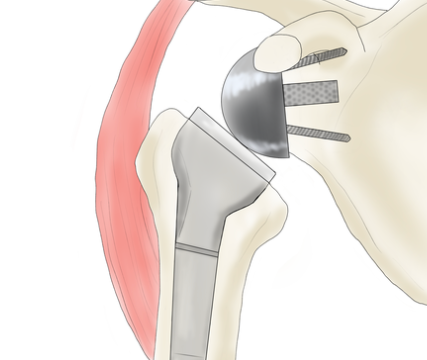

어깨 치환술(Total Shoulder Arthroplasty)

적응증: 이 수술은 심각한 어깨 관절염, 회전근개 파열, 기타 어깨 관절 문제가 있는 환자에게 권장됩니다.

절차: 어깨 전치환술에서는 어깨 관절의 볼(상완골두)과 소켓(관절와)을 모두 금속과 플라스틱으로 만든 인공 부품으로 교체합니다.

혜택: 어깨 치환 수술은 만성 어깨 통증을 완화하고, 어깨 이동성을 향상시키며, 환자의 머리 위 활동 수행 능력을 향상시킬 수 있습니다.